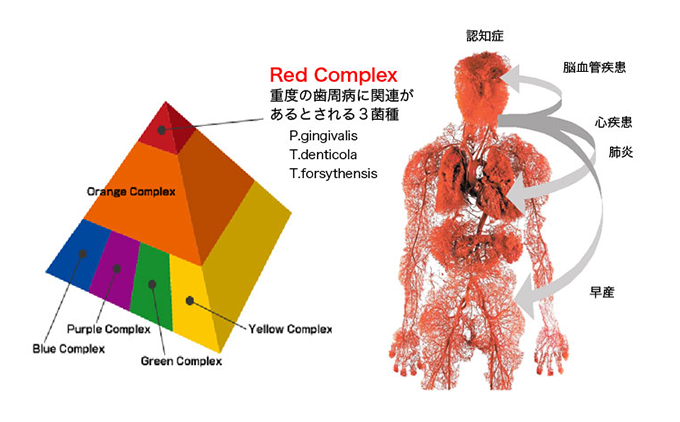

お口の中には、

500~700種類の菌が存在すると

言われており、

その中でも

口腔内の病気と関係の深い原因菌は、

すでに医学的に特定されています。

それぞれの特徴について下記を

ご覧ください。

デンマークの臨床研究で、6~7mmの5ポケットに対し、処置前の歯周病原菌と、SRP&LAD治療をしてから一か月後の歯周病原菌の占める割合を調べたものがあります。

もっとも病原性が高いと言われるRedcomplexが63%から13%へ減少し、菌層も病原性の低いものへと置き換わったという結果がでました。

抗菌療法の担う役割は、Red Complexと呼ばれる歯周病原菌による感染を除去する事にあります。その上で、細菌に感染した歯石や根面を、デブライトメントにより除去する必要があるのです。